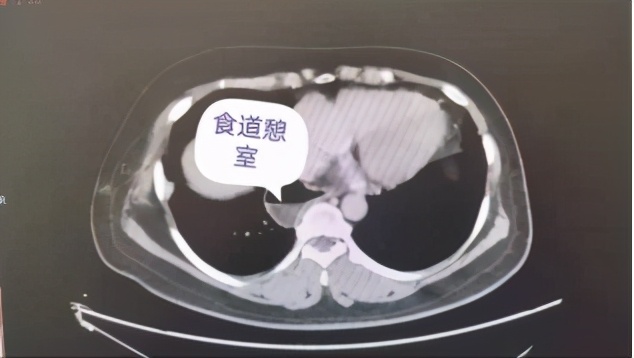

患者耿某,女,46岁,盘州市松河乡人,1个月前无明显诱因出现进食后胸部疼痛,为阵发性烧灼样疼痛,到该院心胸泌尿外科住院治疗。据悉,耿某一年前接受过纵膈肿瘤切除手术。住院期间完善胸腹部CT、胃镜、食道造影检查,明确诊断为“食道下段憩室”。

本次手术由该院副院长付强主刀,该科团队配合实施完成。手术过程分两步:首先,取左胸后外侧切口沿第七肋上缘进胸,探查见食管下段憩室大小为7cmX4cm,充分分离后切除;而后行食管与胃部进行吻合重建术,术中出血较少,患者各生命体征均正常,手术历时5个小时,非常成功。术后,在医护人员的精心护理和治疗下,耿某恢复良好。